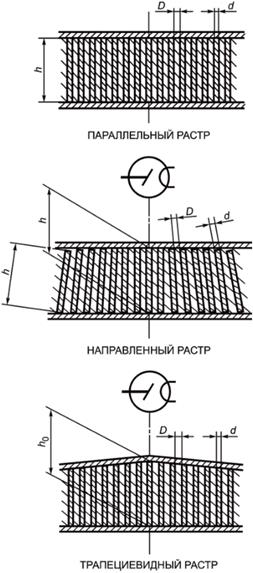

ОТСЕИВАЮЩИЕ РАСТРЫ обычно состоят из полос (ламелей) материала высокого поглощения шириной d и высотой h, расположенных на равном расстоянии друг от друга D (см. рисунок 1).

Рисунок 1 - Конструкция ОТСЕИВАЮЩИХ РАСТРОВ

Высота ламелей h бывает постоянной по всей площади ОТСЕИВАЮЩЕГО РАСТРА либо уменьшается в ТРАПЕЦИЕВИДНОМ РАСТРЕ к краям от наибольшей высоты, обозначаемой h0.

Примечание - D и d измеряют на входной поверхности растра.

3.1.3 ПАРАЛЛЕЛЬНЫЙ РАСТР (PARALLEL GRID): ЛИНЕЙНЫЙ РАСТР, в котором плоскости поглощающих ламелей параллельны друг другу и перпендикулярны входной поверхности.

3.1.4 НАПРАВЛЕННЫЙ РАСТР (FOCUSED GRID): ЛИНЕЙНЫЙ РАСТР, в котором плоскости поглощающих ламелей сходятся на ФОКУСНОМ РАССТОЯНИИ в прямую линию.

3.1.5 ТРАПЕЦИЕВИДНЫЙ РАСТР (TAPERED GRID): ЛИНЕЙНЫЙ РАСТР, в котором высота поглощающих ламелей уменьшается по мере увеличения расстояния между поглощающими ламелями и ИСТИННОЙ ЦЕНТРАЛЬНОЙ ЛИНИЕЙ. Уменьшение происходит симметрично по отношению к ИСТИННОЙ ЦЕНТРАЛЬНОЙ ЛИНИИ.